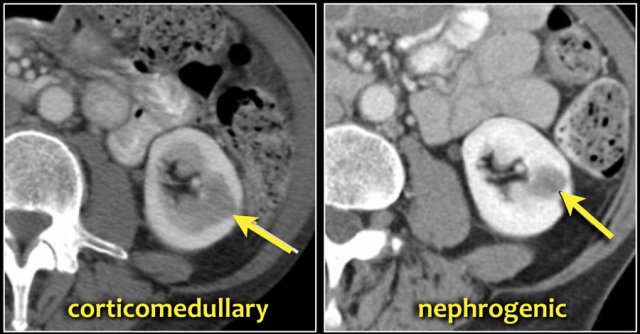

A typical feature of clear cell carcinoma is strong enhancement in the corticomedullary phase.

This can be difficult to assess when the lesion is small and located in the renal cortex, which also enhances strongly.

The nephrogenic phase is therefore the most sensitive phase for the detection of these lesions, as the renal parenchyma enhances homogeneously and more intensely than the tumor (figure).

Prominent columns of Bertin, bulging of the renal contour and focal renal hypertrophy can look like a renal mass on ultrasound, unenhanced images and CT in the nephrogenic phase.

In the corticomedullary phase the normal corticomedullary pattern in these pseudotumors can be appreciated, distinguishing them from real lesions.

Here is another case.

In the nephrogenic phase one could argue there is a lesion in the left kidney.

In the corticomedullary phase however it is clear that this is a pseudotumor.

The corticomedullary phase 25-40 sec post injection is strongly recommended. It helps to differentiate tumor from pseudotumor and to assess enhancement of a lesion.

In this phase however a tumor located in the renal medulla can have the same attenuation as the surrounding parenchyma (figure).

Therefore the nephrogenic phase (±100 sec post injection) is the most important phase for the detection of a tumor.